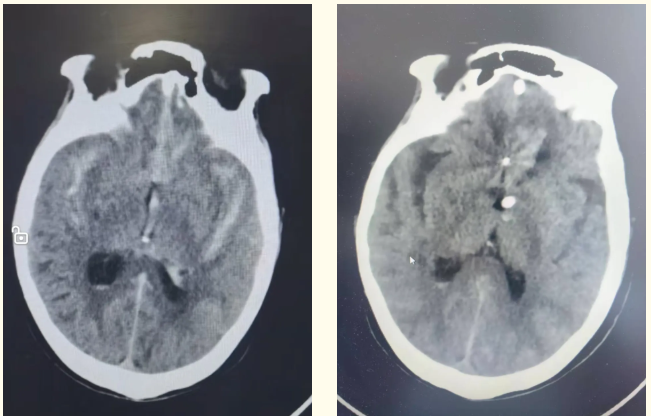

近期,83岁的吴大爷突发意识障碍,家属紧急将其就近送到即墨区中医医院救治。接诊医生迅速为患者安排了相关检查,并给予对症治疗。颅脑CT显示患者为自发性蛛网膜下腔出血、脑积水,患者出血量大,病情危重。即墨区中医医院神经外科主任、副主任医师杨为卓会诊后,考虑患者为脑动脉瘤破裂出血可能性比较大。因患者高龄,体质较差,杨为卓与患者家属充分沟通后,决定进行脑血管造影明确诊断。造影证实患者为前交通脑动脉瘤破裂出血。杨为卓立即带领神经外科团队为患者进行了破裂脑动脉瘤介入手术。因为患者脑出血量比较大,脑积水严重,手术团队在介入栓塞后,又为患者进行了侧脑室钻孔置管引流。手术后,患者恢复良好,神志转清后,转到普通病房进一步恢复治疗。

▲近期患者甲术前、术后颅脑CT影像。